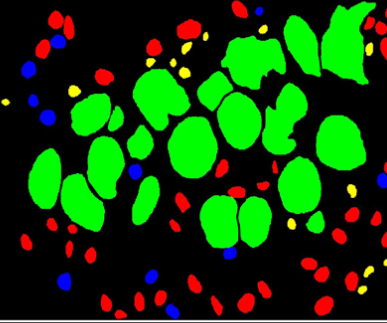

4.1.2 MoNuSAC

Multi-Organ Nuclei Segmentation and Classification Challenge has been organized with an aim of detecting, segmenting, and classifying different types of nuclei around the tumor matrix and it holds a special importance in characterizing the tumor micro-environment for cancer research and prognostication thus freeing up pathologists time for other major tasks. This also helps in reducing chances of errors being caused while doing this task manually. For this challenge a dataset having 46000 nuclei of 4 different organ and types have been used. Majority of participant have used following techniques for achieving better results including pre-processing by color normalization, data augmentation, major CNN architectures used includes U-Net [31], FPN [34], FCN [33], HoVer-Net [38], DenseNet [37], VGG-Net [36] and Efficient-Net [39] followed by watershed, morphological operations and thresholding techniques for post processing to fatigue and subjectivity.